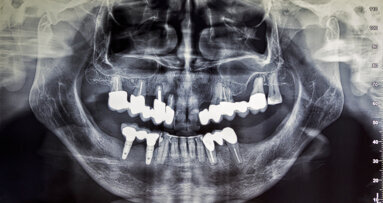

MINNEAPOLIS, US: Patient shielding during dento-maxillofacial radiography is a long-standing practice that is believed to help reduce the risk of radiation-caused hereditary effects and radiation-induced cancer. However, the American Academy of Oral and Maxillofacial Radiology (AAOMR) has recently published a position statement in which it recommends discontinuing the use of protective gear during such imaging procedures. It stated that dental radiographic procedures induce no heritable effects in humans and deliver only a negligible radiation dose to the gonads and foetus. Additionally, it stated that the risk of radiation-induced cancer during such procedures is insignificant. The report provides the most up-to-date guidance for radiation safety and protection in oral and maxillofacial imaging.

Although dental radiography is an indispensable part of dental examinations and treatments, owing to its perceived negative health effects, many patients shy away from it. This is especially true for pregnant women and paediatric patients. For such patients, protective gear such as a lead apron or thyroid collar has a profound psychological impact by helping alleviate patients’ and parents’ concerns regarding the dangers of radiation.

According to the researchers, dental radiography has greatly evolved, and the newest technology poses no threat to patients’ health. They explained that since most radiation exposure results from internal scattered radiation, shielding does not actually protect organs positioned outside of the imaged field. In fact, the report states that protective gear for dental radiology can even potentially increase the radiation dose to the patient by obscuring the anatomy being imaged when placed incorrectly, requiring a retake. Additionally, a lead apron may be contaminated with saliva and thus carry infection control risks if not properly disinfected.